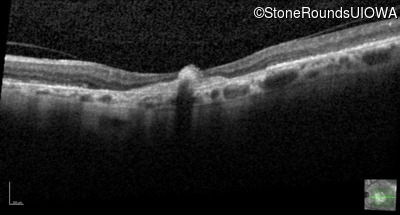

Optical Coherence Tomography - Right - 20/100

Exemplar / OCT Stack

OCT Stack